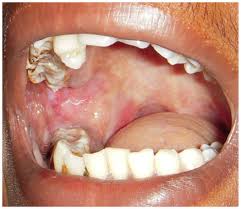

- Erythroplakia: Red patches in the mouth

- Submucous fibrosis: A progressive scarring disorder linked to betel products